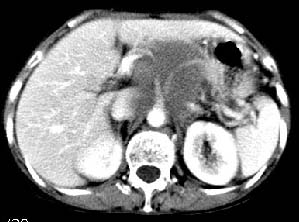

主动脉-胰腺间隙可见巨大分叶状软组织肿块影,包绕腹主动脉、腹腔干及其分支、腔静脉等大血管,增强呈无明显强化,临近脏器明显受压移位,增强示有分界。肝右叶可见局限性低密影,边缘清楚。

考虑腹膜后淋巴瘤。

影象表现:平扫,首先可见胃壁明显增厚,内外边缘清晰,外缘光滑,内边缘不归整,同时胃腔明显缩小。

再看从肠系膜根部到胰腺后主动脉及上腔静脉周围可见相连的较大的软组织肿块影,形态不规则,呈明显

的大小不等的分叶状,其中密度较均匀但其中可见条状低密度区,肿块边缘比较清晰周围的小肠受压移位

明显且堆积。

增强所见,腹腔动脉,肠系膜上动静脉被肿块包绕,结合平扫的条状低密度区恰好位于血管周围,较大的

肿块强化不明显(遗憾的是没有标上ct值)但胃壁强化的十分明显。